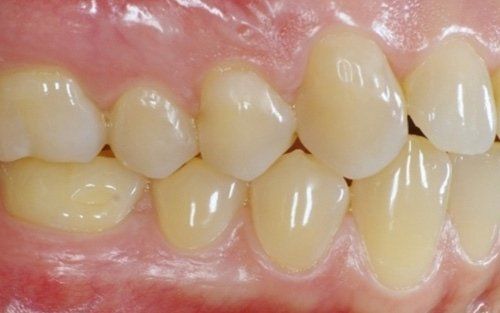

Erosion is the phenomenon whereby dental enamel undergoes a gradual dissolution due to the constant presence, in the oral cavity, of acidic substances mainly from certain types of beverages (cola, iced tea, sports supplements, etc.) or from the stomach (gastroesophageal reflux, vomiting induced in bulimic/anorexic patients).

The constant presence of acidic substances causes the gradual loss of the hard tissues of the tooth

and the consequent modification of both the aesthetics of the tooth and its dimensions. The patient often begins to stop smiling, ashamed of the appearance their teeth have taken, in addition to frequently experiencing dental sensitivity that develops proportionally to the progression of the process. Sometimes this phenomenon is associated with